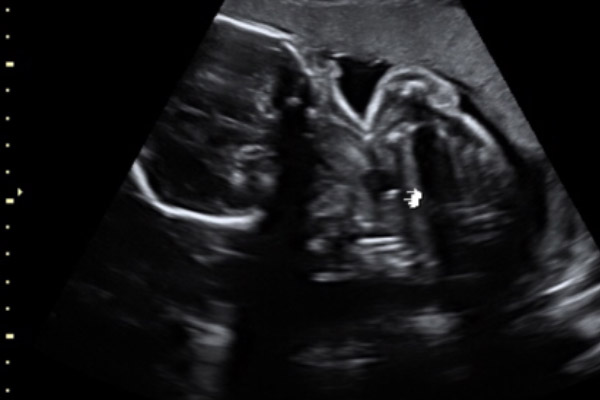

Para os casos mais graves, com herniação do fígado no tórax e/ou RCP<1,0, pode ser realizado um procedimento no feto chamado de oclusão traqueal. Por via endoscópica, é colocado um balão na traquéia do feto entre 24 e 28 semanas de gestação.

E qual é o papel do balão traqueal no feto?

Ele promove um aumento no volume do pulmão fetal, o que melhora a chance sobrevida pós-natal nos casos de HDC grave. A chance de sobrevida com alta do bercário para as crianças que fizeram o tratamento é de 50 % (o que seria próximo a zero se fosse realizada conduta expectante).